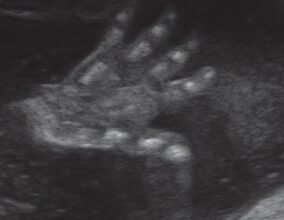

Ecografía de 18 semanas: dos manitas con la ecografía en 3D.